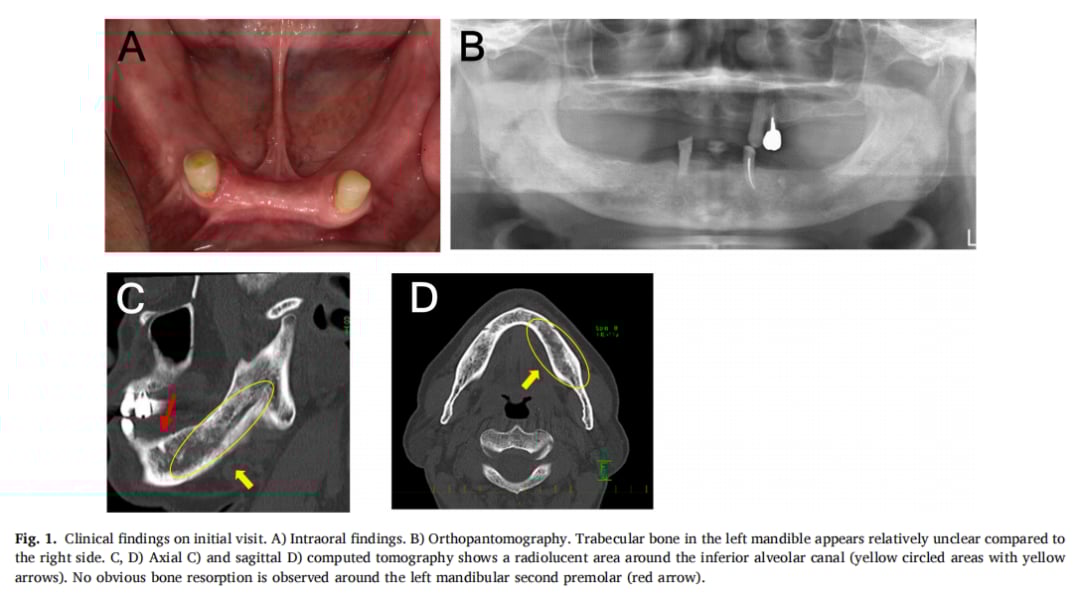

初次检查时,医生发现患者下唇部分区域存在感觉异常,但口腔黏膜并无明显的红肿或炎症迹象。然而,口腔全景片和CT扫描却揭示了异常:左下颌骨的骨小梁结构模糊,松质骨内存在边界不清的低密度区域。这些影像学特征并不像典型的牙源性感染或骨髓炎,反而指向了恶性肿瘤的可能性。

▲图1 初诊时的临床发现